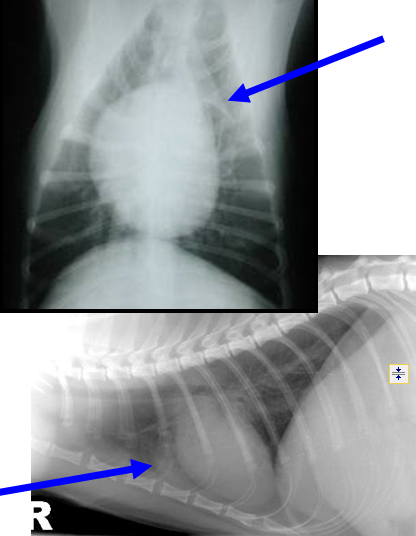

What can be seen here?

Mediastinal mass/fluid

Pleural fluid as lung lobes pushed away from spine

There is a mass here – our mass effect can help – trachea is dorsally elevated and compressed, something solid doing this

Pleural fluid and mediastinal mass